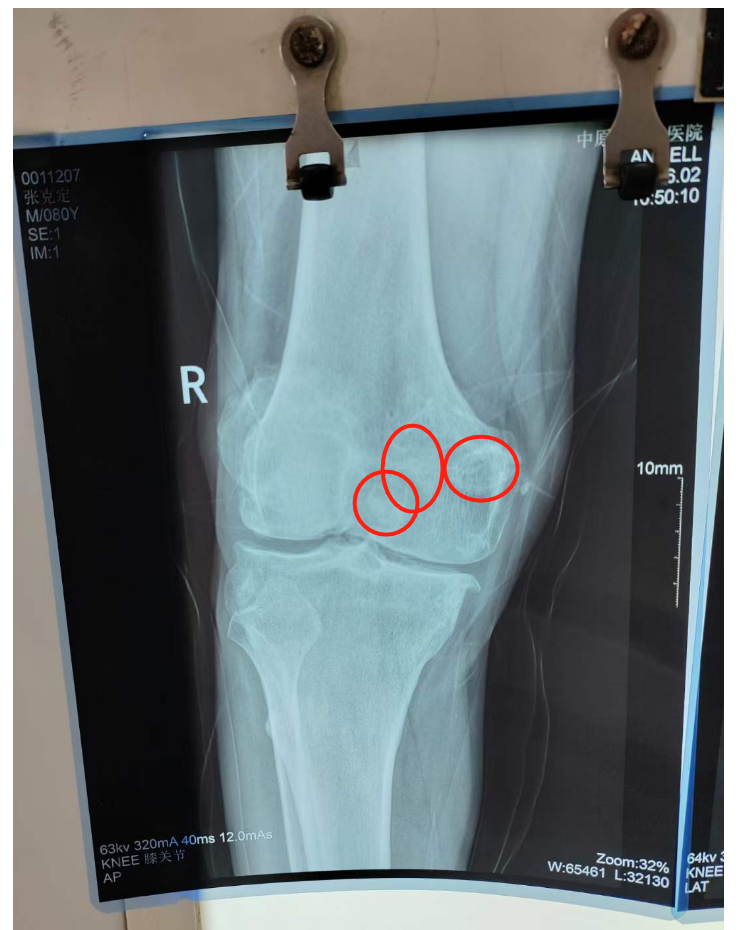

在当地医院做了x线检查, 当地医生发现 王师傅的膝关节里密密麻麻的